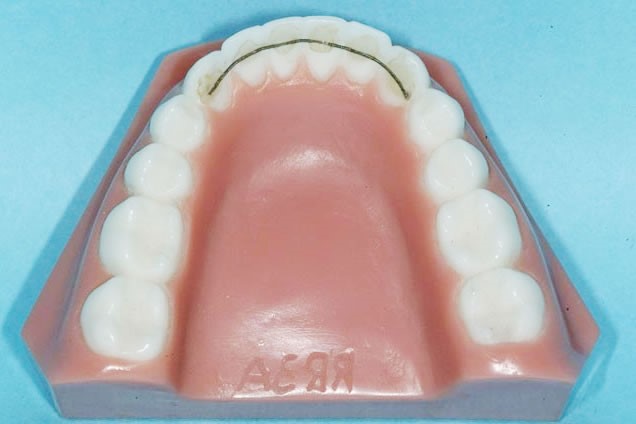

保定装置

治療期間:2年以上

装置料:なし(動的治療時に使用した装置料に含まれます。)

一期治療での目標達成後は、後戻り(歯が元の位置にもどろうとすること)を防止し、残っている乳歯が永久歯へスムーズに交換できるようにするために、保定装置を使用する必要があります。お口の状態によって使用する装置は異なり、矯正歯科医がベストな装置を決めていきます(基本的に患者様がご選択することはできません)。

子どもの場合、すべての歯が永久歯に生え変わり、成長がある程度落ち着いてくるまでは保定装置の使用が必要です。すべての歯が永久歯に生え変わるのが12~14歳頃となり、男の子だと高校生くらいまで成長が続くことがあります。この時期までは、数か月~1年おきの定期的な観察が必要になります。